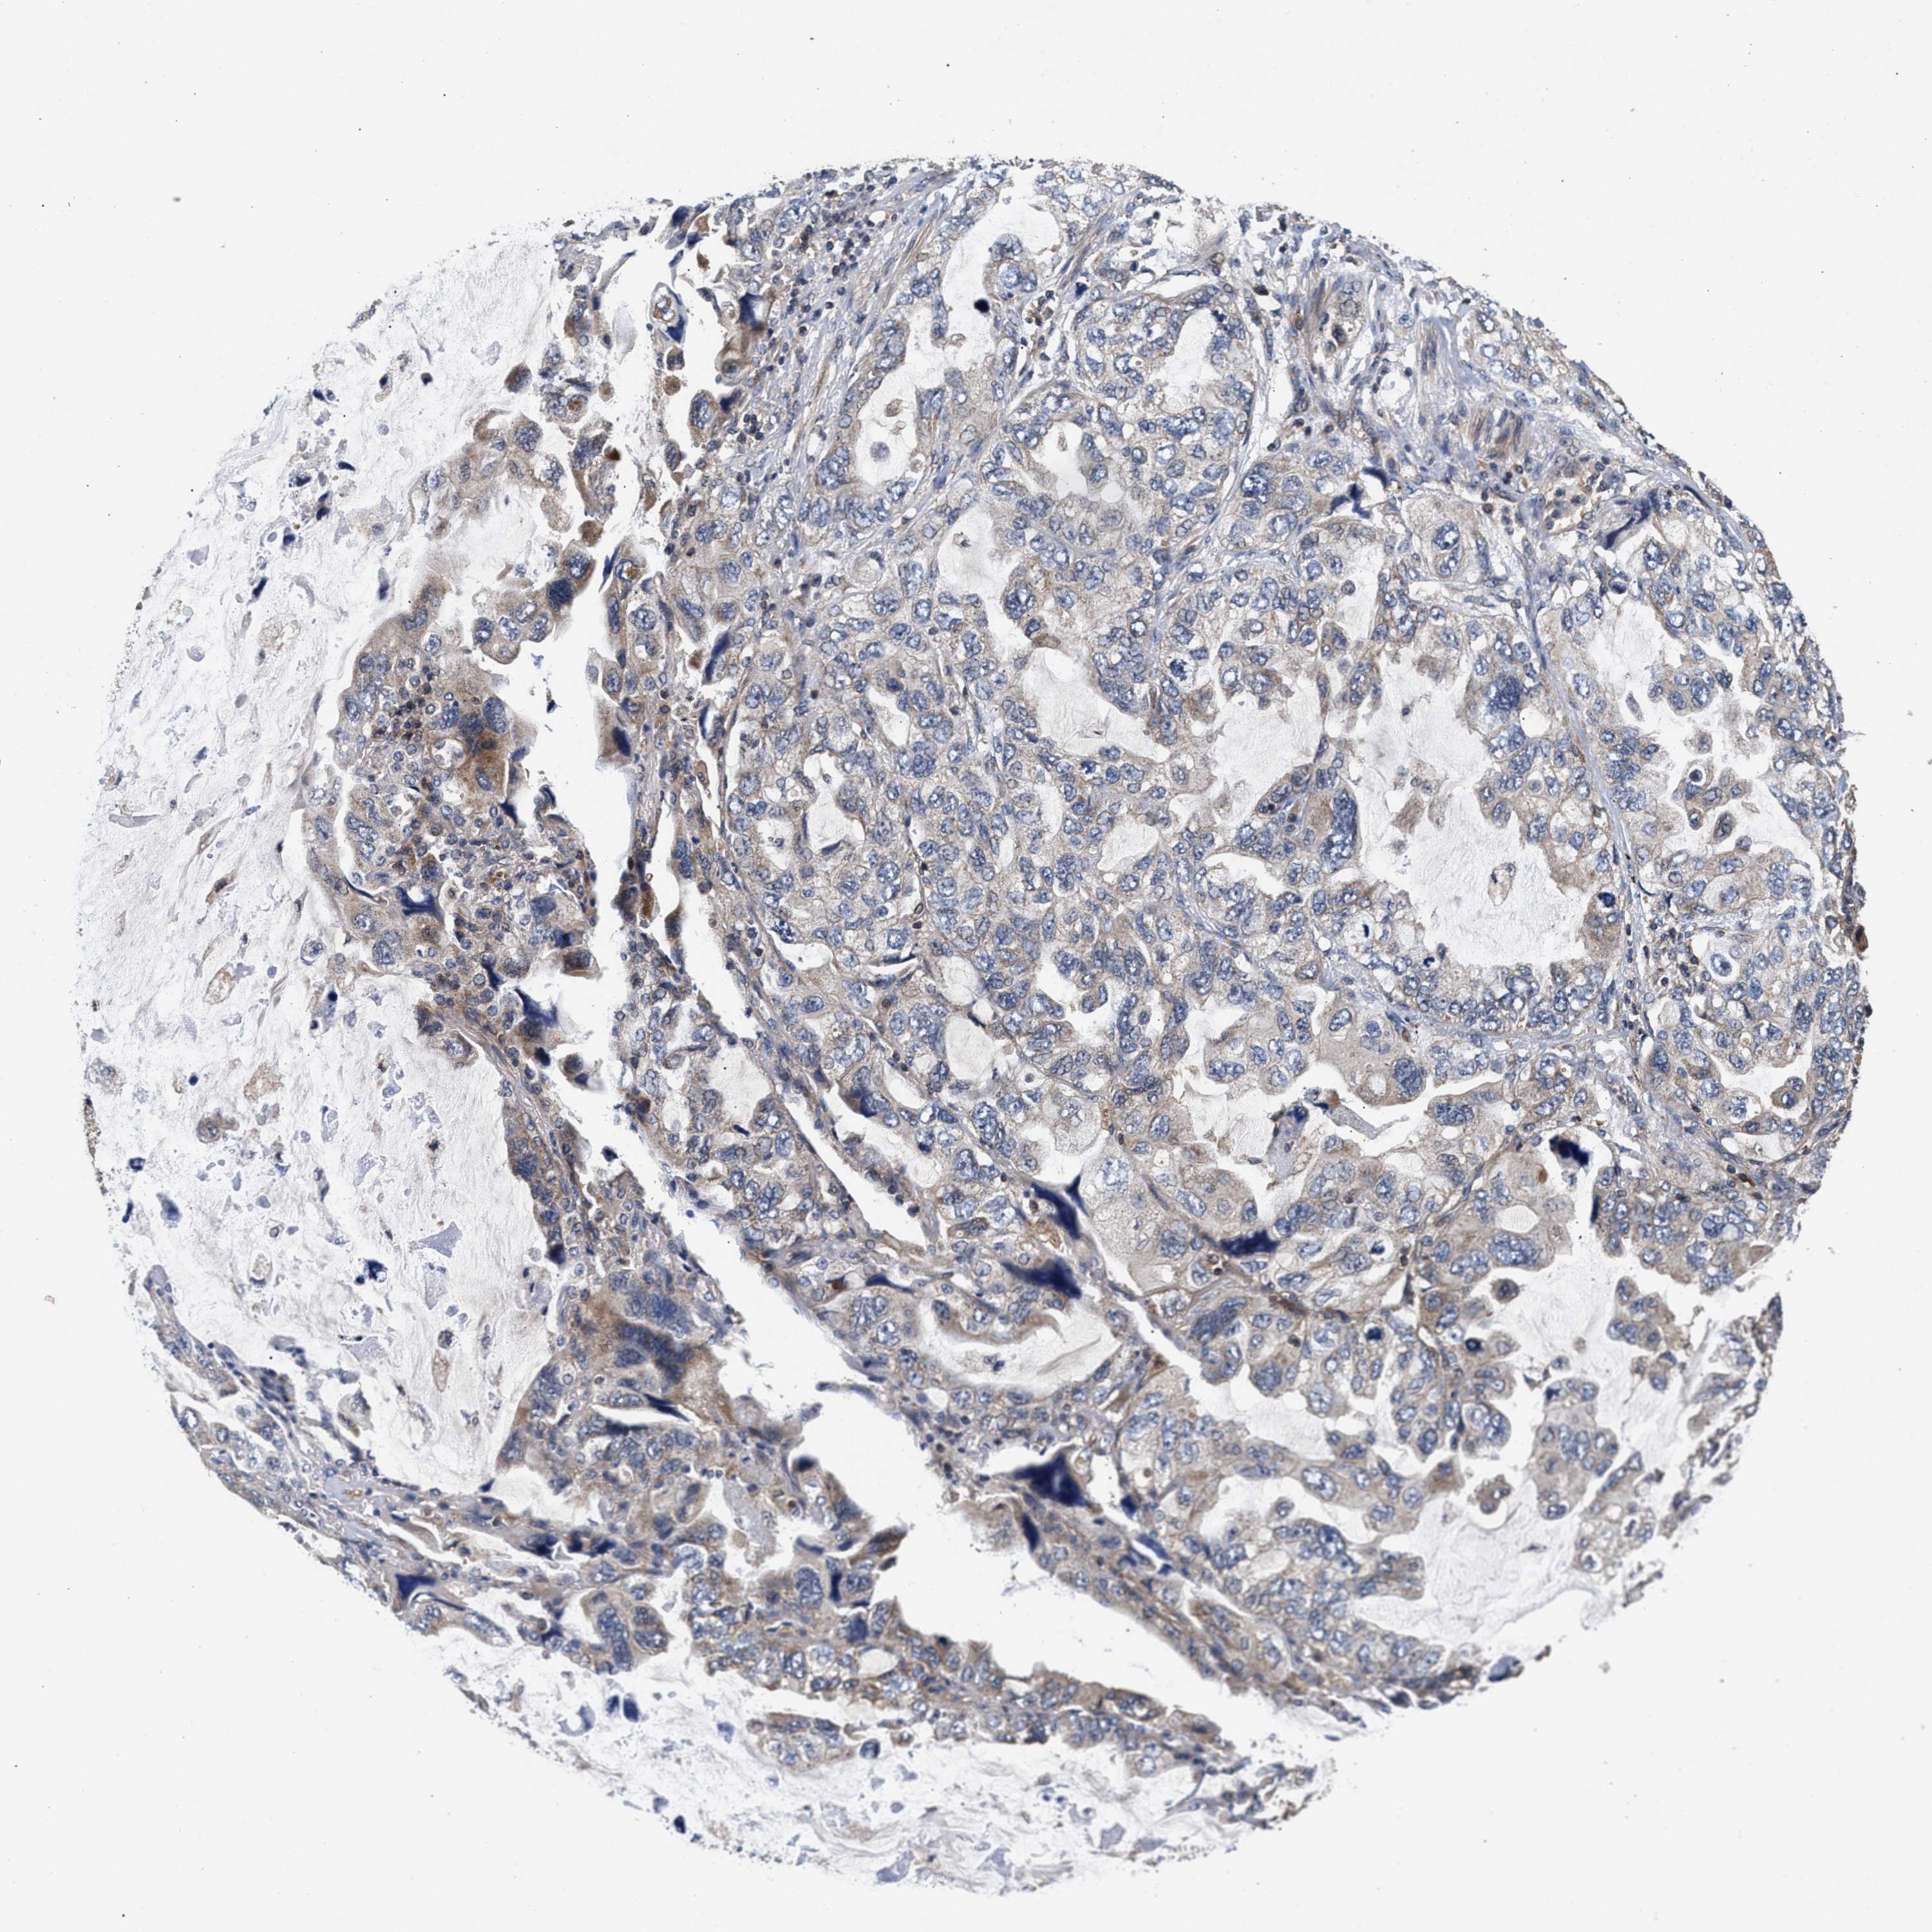

CANCER LUNG CANCER Show tissue menu

LUAD TCGA LUAD VALIDATION LUSC TCGA LUSC VALIDATION PROTEIN LUAD CPTAC PROTEIN LUSC CPTAC PROTEIN EXPRESSION